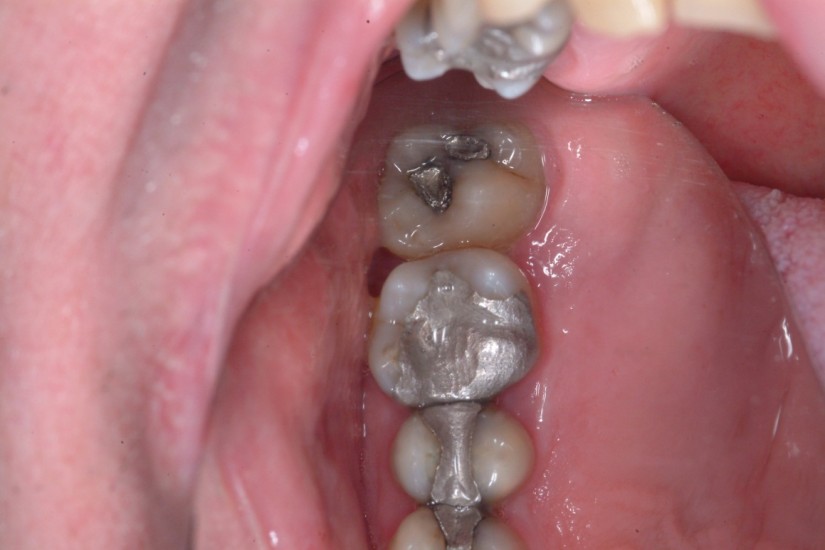

A toothache caused by a broken tooth (tooth fracture) without associated cavity or advanced gum disease. Biting on the area of tooth fracture can cause severe sharp pains. These fractures are usually due to chewing or biting hard objects such as hard candies, pencils, nuts, etc. Sometimes, the fracture can be seen by painting a special dye on the cracked tooth. Treatment usually is to protect the tooth with a crown. However, if placing a crown does not relieve pain symptoms, a root canal procedure may be necessary.